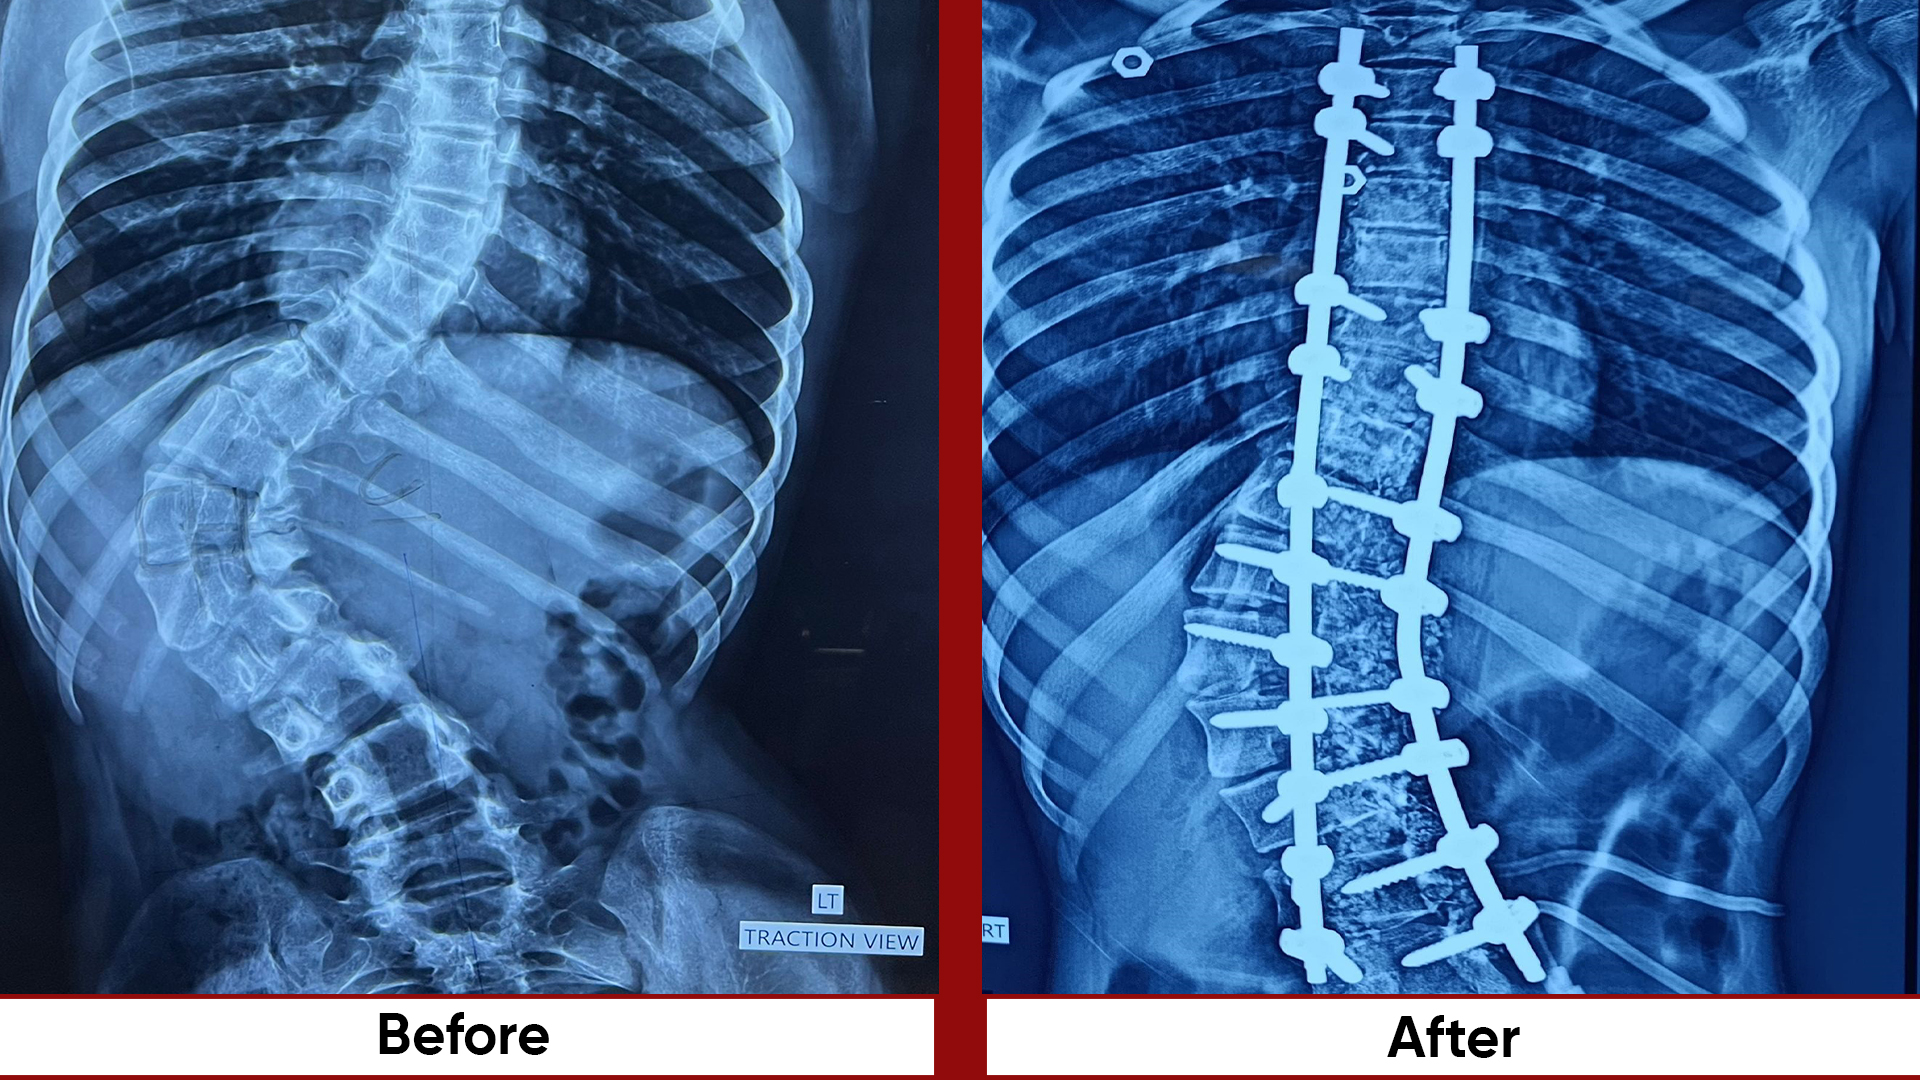

Procedures

• Fracture Management (simple and complex trauma)

• Deformity Correction (limb lengthening, bowlegs, knock knees)

• Osteotomies (bone realignment surgeries)